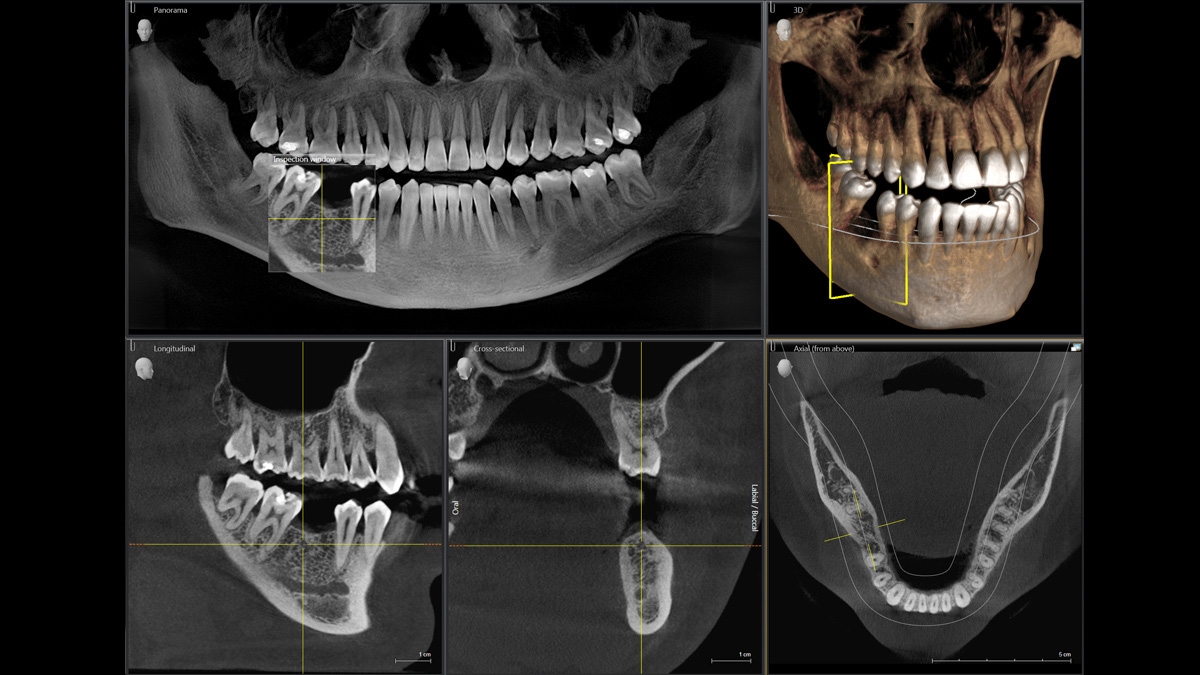

Za použití příslušného senzoru získáte laterální a symetrické předozadní ap/pa kefalo snímky i snímky zápěstí. V případech retinovaných zubů se můžete vrátit zpět k výhodám 3D rentgenů a stanovit jejich přesnou lokaci.